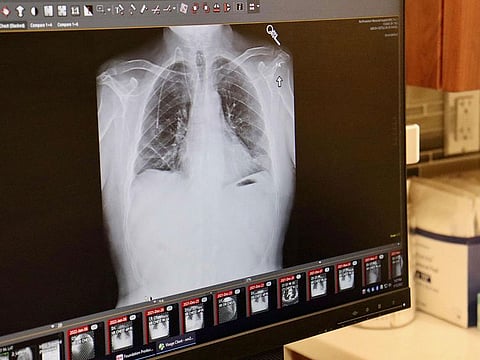

Lung cancer is the second most common cancer worldwide, with 2.2 million new cases in 2020

Lung cancer is the second most common cancer worldwide, with 2.2 million new cases in 2020.